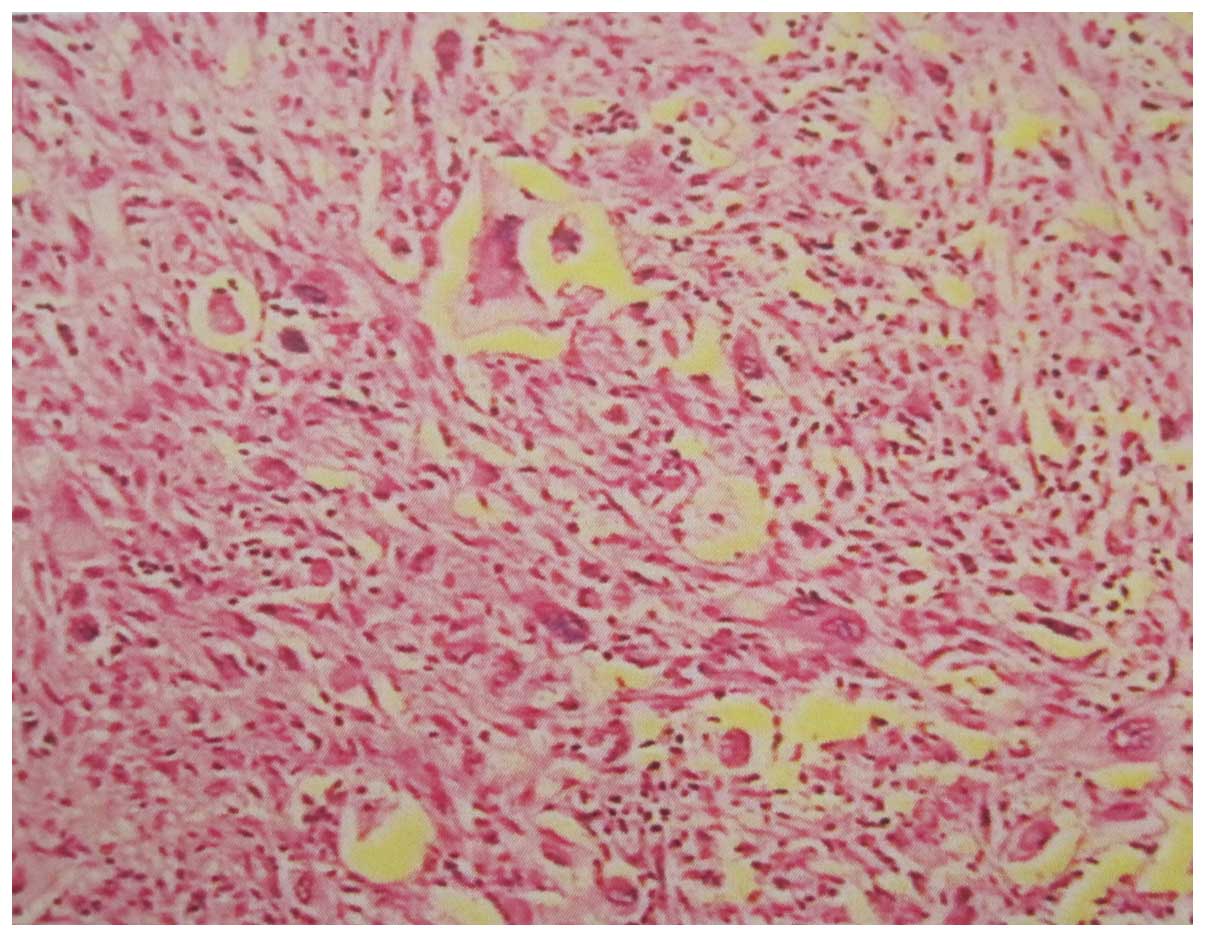

Microscopically, the tumor was identified as a

sarcoma, which demonstrated ovoid and polygonal tumor cells that

were of diffuse distribution with obvious atypia and mitotic

figures. In addition, a combination of numerous giant tumor cells

and fatty tissue with different degrees of differentiation was

observed (Fig. 6).

Immunohistochemistry showed positive staining for S-100 protein and

cluster of differentiation (CD)68, and negative staining for smooth

muscle actin, CD34 and vimentin. The final pathological diagnosis

was a primary dedifferentiated liposarcoma of the femur, and the

dedifferentiated tissue was identified as malignant fibrous

histiocytoma.